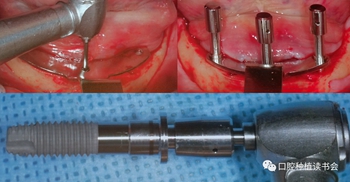

使用超聲骨刀完成骨修整后,使用導(dǎo)板確認是否滿足種植體植入條件,然后使用球鉆定點,2mm先鋒鉆預(yù)備后,測量垂直高度,以確定是否滿足22mm修復(fù)空間的要求。在定位導(dǎo)板上,先預(yù)備中間種植窩,逐級預(yù)備,根據(jù)患者條件確認最后鉆的寬度,植入錐度連接的軟組織水平、平行壁植體,該種植系統(tǒng)是有11.5和13mm的不同長度,以及 4.5和6mm 高度的光滑頸環(huán)平行壁的軟組織水平種植體。(圖7)

圖7 在定位導(dǎo)板引導(dǎo)下,預(yù)備種植窩洞

先植入中央種植體后,卸下定位導(dǎo)板,安裝V形導(dǎo)板,完成兩側(cè)種植體植入,試戴支架確認種植體角度正確,使用光固化樹脂固定預(yù)制件,調(diào)整被動就位后,轉(zhuǎn)移基臺轉(zhuǎn)移種植體位置(圖8)。

圖8 在V形導(dǎo)板引導(dǎo)下,完成兩側(cè)種植體植入,轉(zhuǎn)移種植體位置